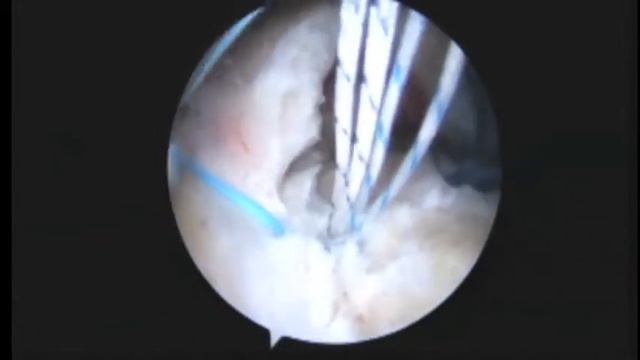

Single row repair with Y Knot RC all-suture suture anchors Modified PITT soft tissue biceps tenodesis, видео от 2024-01-11 загрузил на rutube Подготовка женского тела к вершинам...